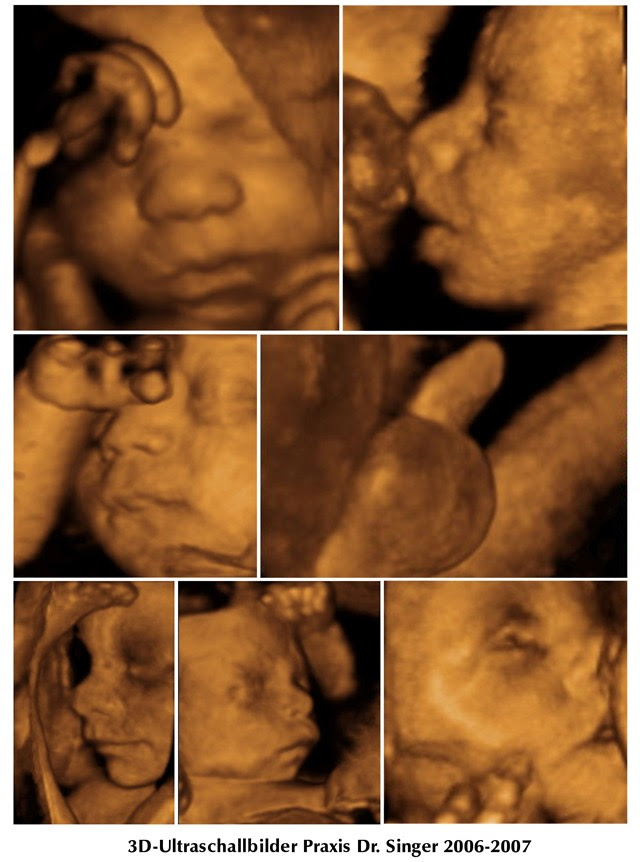

Ritorno alla natura

Da qualche tempo, le campagne pubblicitarie della stampa e della televisione per la nuova generazione di dispositivi ad ultrasuoni ad alta intensità di radiazioni si stanno accumulando. I nuovi dispositivi 3 e 4-D, la cui migliore qualità d'immagine affascina medici, ostetriche e genitori, sono lodati ed elogiati. Oggi

un apparecchio ad ultrasuoni così moderno costa tra CHF 150'000.00 (circa 125.000,00 €) e CHF 200'000.00 (167.000,00€)

e non è difficile calcolare quante applicazioni siano necessarie per recuperare i costi elevati. E così, per anni,

abbiamo osservato un crescente uso di ultrasuoni in gravidanza, senza mai provare l'innocuità delle onde ultrasoniche. Ci si dovrebbe aspettare una simile prova prima che gli